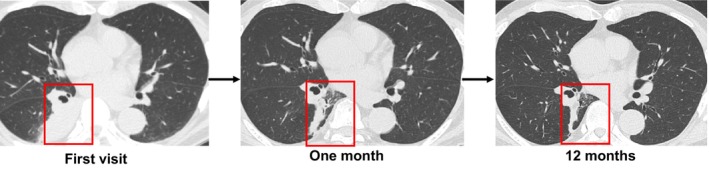

Various endobronchial therapies, as well as complete surgical resection, have recently been reported. Among them, microwave coagulation is a promising endobronchial therapy for a wide range of neoplasms due to its high efficacy and safety. Meanwhile, endobronchial lipoma is a benign tumour that is rarely observed in the lungs. To our knowledge, the efficacy of microwave coagulation has not been reported in the treatment of endobronchial lipoma. Here, we report the effectiveness of endoscopic microwave coagulation therapy in safely resolving atelectasis and cough caused by endobronchial lipoma. Surgical resection was deemed to be unsuitable in this case due to the likelihood of extensive surgery such as right lower lobectomy being required, and comorbidities including poorly controlled diabetes mellitus. There was an elevated risk of perioperative complications. This report presents a new, effective, and minimally invasive treatment option for endobronchial lipoma in endoscopic microwave coagulation to relieve atelectasis.